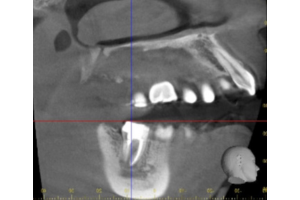

基本情報

| 年齢・ 性別 |

30歳・女性 |

|---|---|

| 主訴 | 主訴:他院で2年程前に入れたジルコニアクラウンが痛む。 ジルコニアクラウンを入れた時にかみ合う上の歯を大きく削られたが、かみ合わせにずっと違和感もある。 部位:右下7番 |

| 治療 内容 |

被せ物を除去しかみ合わせを確認。 再根管治療を行い、根管治療後土台(FBコア)まで入れたらかみ合わせを高さを確保するために歯ぐきを下げる処置(CLP)を行い、経過を診た後に被せ物の型取りをしました。 |

| 治療 期間 |

約6ヶ月 |

| 治療費 | 合計:135,000円 右下7番 ファイバーコア 16,500円 ジルコニアクラウンステイニング無 60,500円 CLP 55,000円 CT算定代約3,000円 (2024年10月現在) |

| リスク・副作用 | ・かみ合わせの高さが高い、きついなどの違和感を被せ物セット後すぐは違和感を覚えることがありますが、1週間程度で慣れて気にならなくなってきます。 ・破折や脱離のリスクを下げるためにもナイトガード(マウスピース)のご使用をお願いしています。 |

| 治療方針 | 他院で入れたジルコニアクラウンの為どのような状態なのかを確認するためにCT撮影して精査しました。 きちんと根充剤が入っていない部分があり、根の部分全周にかなり大きい膿が出来ていました。かみ合う上の歯と当たってしまうことで膿に刺激がいき痛みが出ている状態でした。 被せ物を外して咬合確認したところ、被せ物が高かったようで、外したら本来の正常なかみ合わせになり顎関節の違和感も解消されました。土台も外して再根管治療を行いました。 根管治療中も顎関節の経過を診ながら治療を進めました。 再根管治療後、土台を入れた後に被せ物を入れるスペースを確保するために、歯ぐきを下げる処置を行い経過を5ヶ月程度みました。 顎関節の違和感が解消され、レントゲン撮影し透過像の縮小、治癒がみられたので、被せ物の型取りを行い被せ物をセットしました。 |